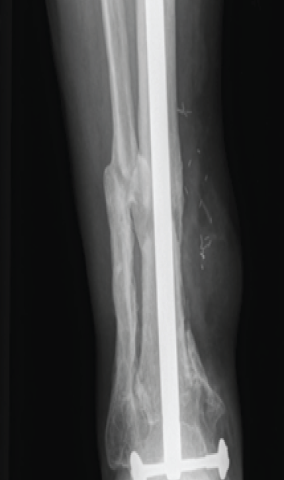

Resection of the infection, appropriate antibiotic therapy over a sufficient period of time, and the stability of the reconstruction have enabled the patient to gradually gain in comfort and autonomy. The current fellow-up is 9 years (Fig. 7).

Figure 7: Post-operative X-ray at 9 years fellow-up.